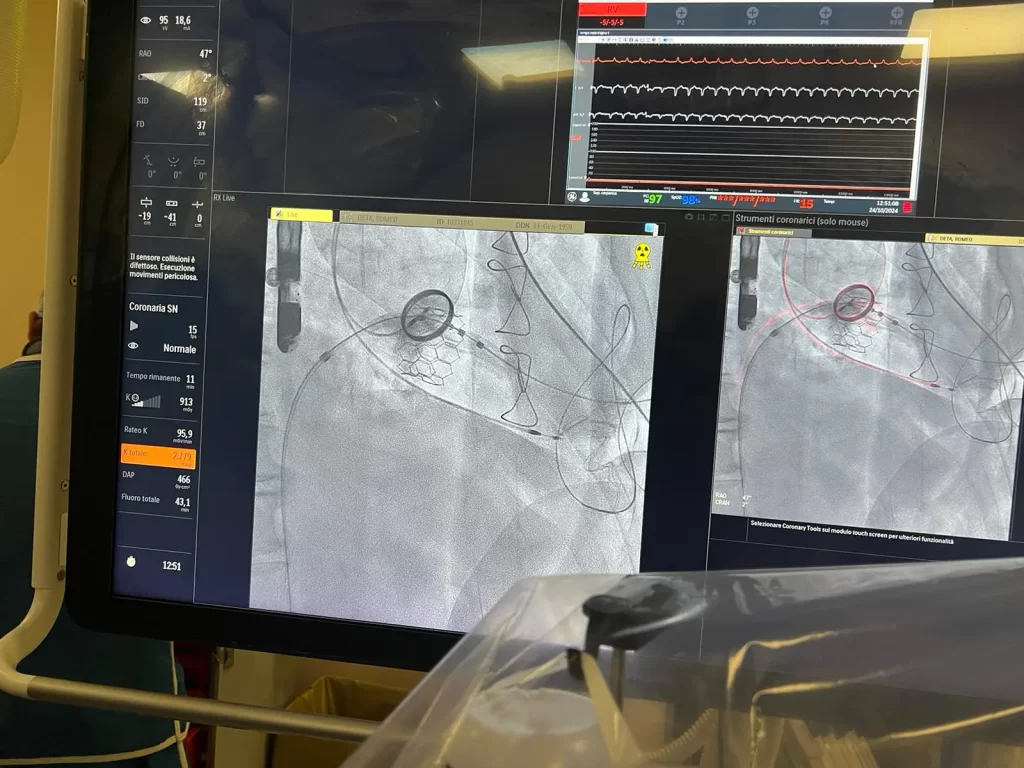

La soluzione individuata rappresentava una via ancora mai percorsa in Italia: l’impianto di una bio-protesi MyVal di diametro molto grande tramite approccio ibrido, costruendo una via di navigazione sicura per posizionare la valvola, riducendo così al minimo l’esposizione al trauma chirurgico e i rischi connessi all’intervento.

“La procedura standard di sostituzione della valvola mitralica può essere percutanea con accesso trans-femorale, ovvero attraverso la vena femorale, o trans-apicale, ovvero con un’incisione del torace di 4-5 centimetri, praticata a livello dello spazio intercostale – spiega il prof. Giuseppe Nasso -. Nel caso specifico della paziente entrambi gli approcci se utilizzati in maniera isolata avrebbero comportato un elevato rischio di complicanze: la via trans-apicale da sola, infatti, risultava troppo invasiva (per il diametro ampio della nuova protesi) mentre l’approccio trans-femorale troppo poco stabile, con il rischio che la valvola biologica aprendosi si disallineasse all’interno del ventricolo. Abbiamo quindi studiato una procedura percutanea con ultra mini-toracotomia (un taglio estremamente ridotto sul torace) per raggiungere l’apice del ventricolo sinistro in cui è stata introdotta una guida molto sottile. Successivamente, è stata fatta passare una seconda guida dalla vena femorale che è stata poi unita alla prima attraverso un “cappio” creando così una vera e propria “teleferica” con partenza dalla vena femorale e uscita dall’apice del ventricolo sinistro. Su tale teleferica la valvola biologica “balloon expandable” ha potuto viaggiare, entrando dalla vena femorale sino a raggiungere l’anello mitralico, su cui è stata posizionata ripristinandone il corretto funzionamento”.

MyVal è una valvola cardiaca transcatetere di nuova generazione espandibile tramite palloncino, che grazie alle dimensioni ridotte delle cannule, alla maggiore precisione dell’impianto e alla sua maneggevolezza consente una migliore manovrabilità attraverso arterie di calibro ridotto e un dispiegamento preciso. Queste caratteristiche, combinate con una strategia chirurgica mai impiegata prima in Italia, hanno consentito di poter intervenire sulla paziente efficacemente e in sicurezza.